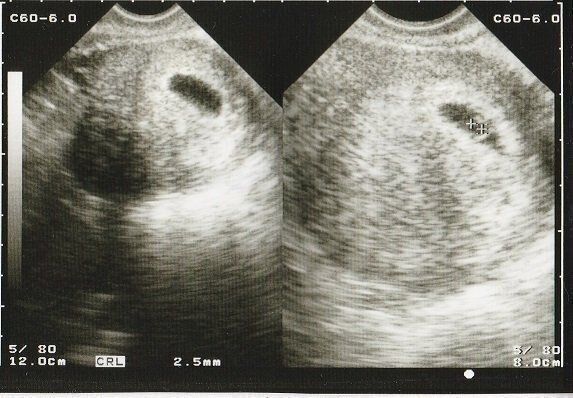

ちゃじゅびさんの妊娠6週目のエコー写真 胎芽が見える

胎嚢が大きくなり、そのなかに胎芽(7週未満の赤ちゃん)が確認できるようになりました。